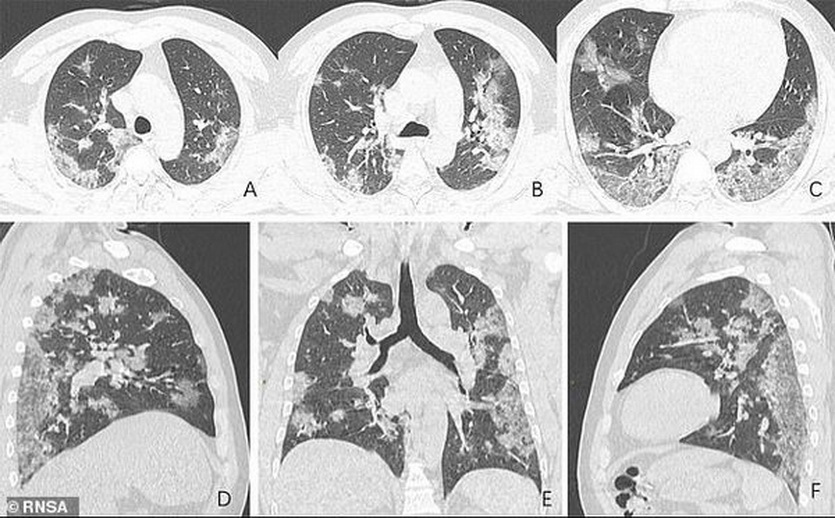

COVID виден на томограмме даже не специалисту

Если бы не эпидемия COVID, большая часть жителей нашей страны даже не услышала бы о томографии, и уж точно не столкнулась с ней в жизни. И дело не только в цене.

Пресловутый COVID во многих случаях первично диагностируется уже на обычных рентгеновских снимках. То же с другими проблемами легких.